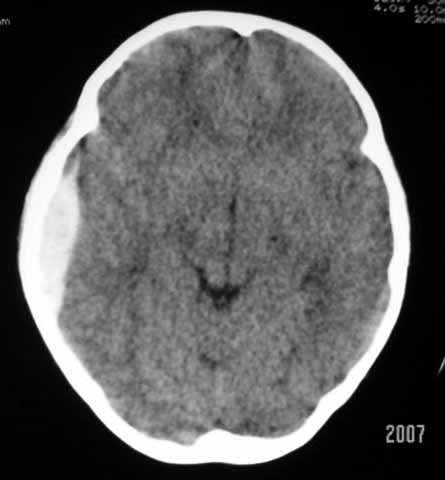

以下是引用why7912在2007-9-1 13:29:00的发言:[br]右侧颞部硬膜外血肿,左侧颞底蛛网膜囊肿,建议观察骨窗

以下是引用wqs571018在2007-9-1 14:57:00的发言:[br]右侧颞部硬膜外血肿,左侧颞底蛛网膜囊肿。